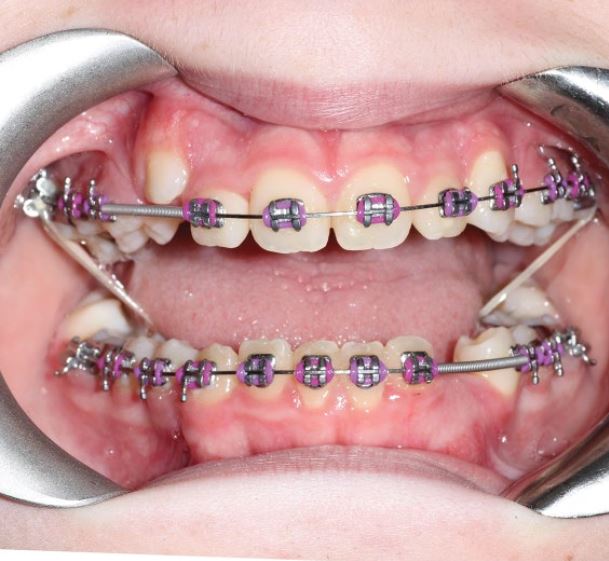

Ca lâm sàng 2: xương và răng hạng I, cắn sâu.

Nền xương hạng I, góc mặt phẳng hàm dưới hơi mở, trục răng cửa hàm trên và hàm dưới dựng đứng, cắn sâu và chen chúc răng cửa dưới.

Mục tiêu điều trị bao gồm nới rộng cung răng kèm thêm mài kẽ (nếu cần), giải cắn sâu và sắp đều răng.

Răng cối và răng nanh đều đạt hạng I, khớp cắn sâu đã được cải thiện.

Profile mặt của bệnh nhân vẫn hơi lõm do cằm quá nhô.

Bệnh nhân được khuyến cáo nhổ răng khôn về sau.